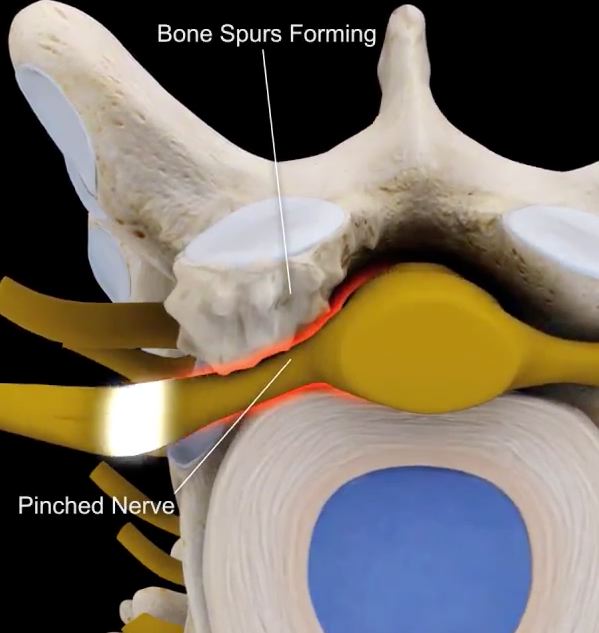

Bone Spur – Osteophytes, Causes, Signs, Symptoms & Treatment

Bone Spur – Osteophytes, Causes, Signs, Symptoms & Treatment

Bone spurs in neck (cervical osteophytes): Causes, symptoms, diagnosis …

Arthritis (Spine) And Bone Spurs

Foraminal Stenosis of the Spine | Bone Spur | Dr. Donald Corenman …